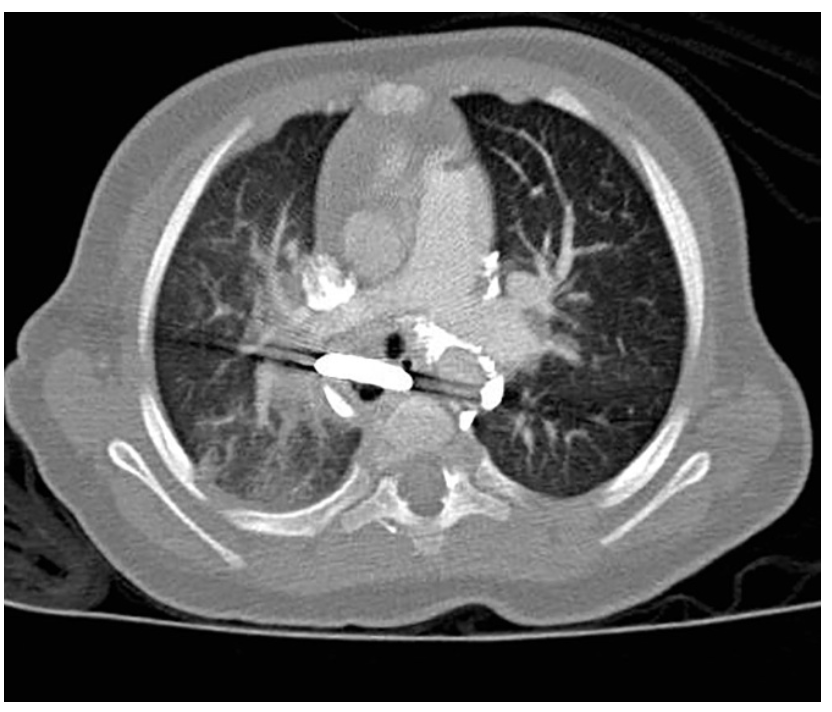

And possibly due to some weird impulse that seems to have travelled across space and time itself, the patient gets an X-ray which shows a button battery and there is just enough in the story to make people look a little harder with a CT scan.

And it’s fair to say that a patient with symptoms of complications possibly weeks down the track a moment for pause is required. Partly because finally we’re back at the part of the talk that is actually about acquired tracheo-oesophageal fistula. Which was supposed to be the point I recall.

Perhaps the thing to do at this point is actually to take a step back from acquired TOF specifically and talk more broadly about anaesthesia for tracheo-oesophageal fistula. It turns out that there isn’t necessarily a lot of agreement on what you should do. A little while back Knottenbelt et al looked retrospectively at TOF anaesthesia across 101 patients in the Oz/NZ context. In their series, 32% had an IV induction, 68% had an inhalational anaesthetic and 64% of the patients were maintained with spontaneous ventilation until control of the fistula.